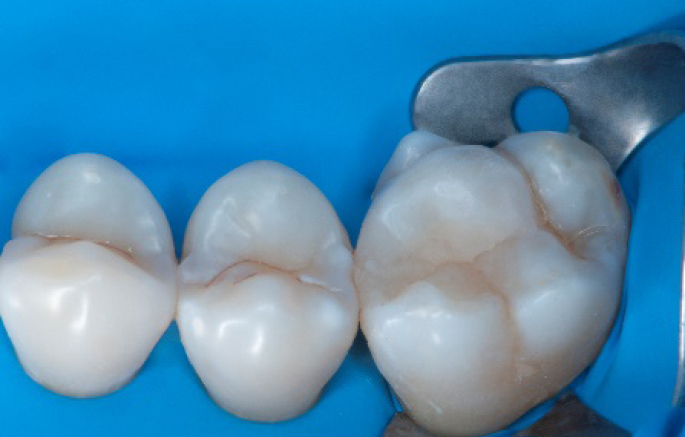

Step 10:

The situation after the application of SDR® flow+ material.

Step 11:

Occlusal surface restored using Spectra ST4 composite in shade A2.